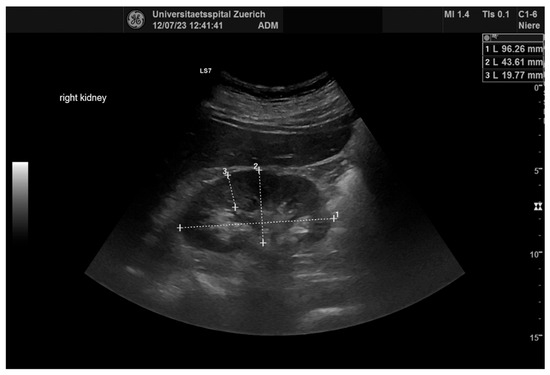

2.4. Ultrasonography

| Renal Parameters (n = 64) | Pre-Operative | Post-Operative | p |

| Length (mm) | 107.1± 13.8 | 107.9 ± 14.5 | ns |

| Wide (mm) | 52.4± 7.9 | 52.9 ± 7.8 | ns |

| Parenchymal margin (mm) | 18.3 ± 3.2 | 18.6 ± 2.8 | ns |